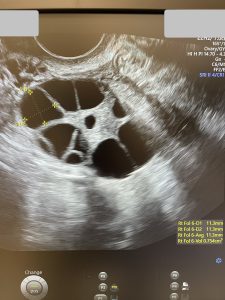

· O rezervă ovariană incredibilă (pentru aproape 42 de ani!): AMH de 4,1 ng/ml în urmă cu 2 ani; la ecografie, un AFC de 33!

La momentul în care scriu aceste rânduri, am făcut deja și a treia stimulare, am obținut 16 ovocite și 6 blastociști. Toți au fost testați PGT-A și așteptăm să vină rezultatul testării…